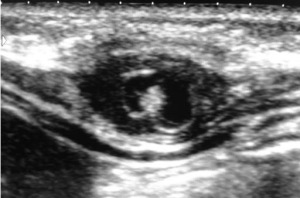

Цистицеркоз диагностируют при помощи УЗИ, рентгена, КТ, МРТ и биопсии. На УЗИ хорошо видно кисту и сколекс цистицерка в мышцах и подкожной клетчатке. На рентгене видно кальцификаты. КТ и МРТ полезны для определения точного расположения цистицерка. На КТ лучше видны мелкие кальцинаты. На МРТ лучше видно сколекс и кисту.

| Фото. Цистицерки в мышцах на УЗИ. А, Б У ребенка безболезненная припухлость в правом подреберье. На УЗИ очаг (16,5х7,5 мм) с кистозным компонентом (6,3х4 мм) и гиперэхогенным (белым) включением внутри (стрелка). Диагноз цистицеркоз передней брюшной стенки. В цистицерк в икроножной мышце. | ||